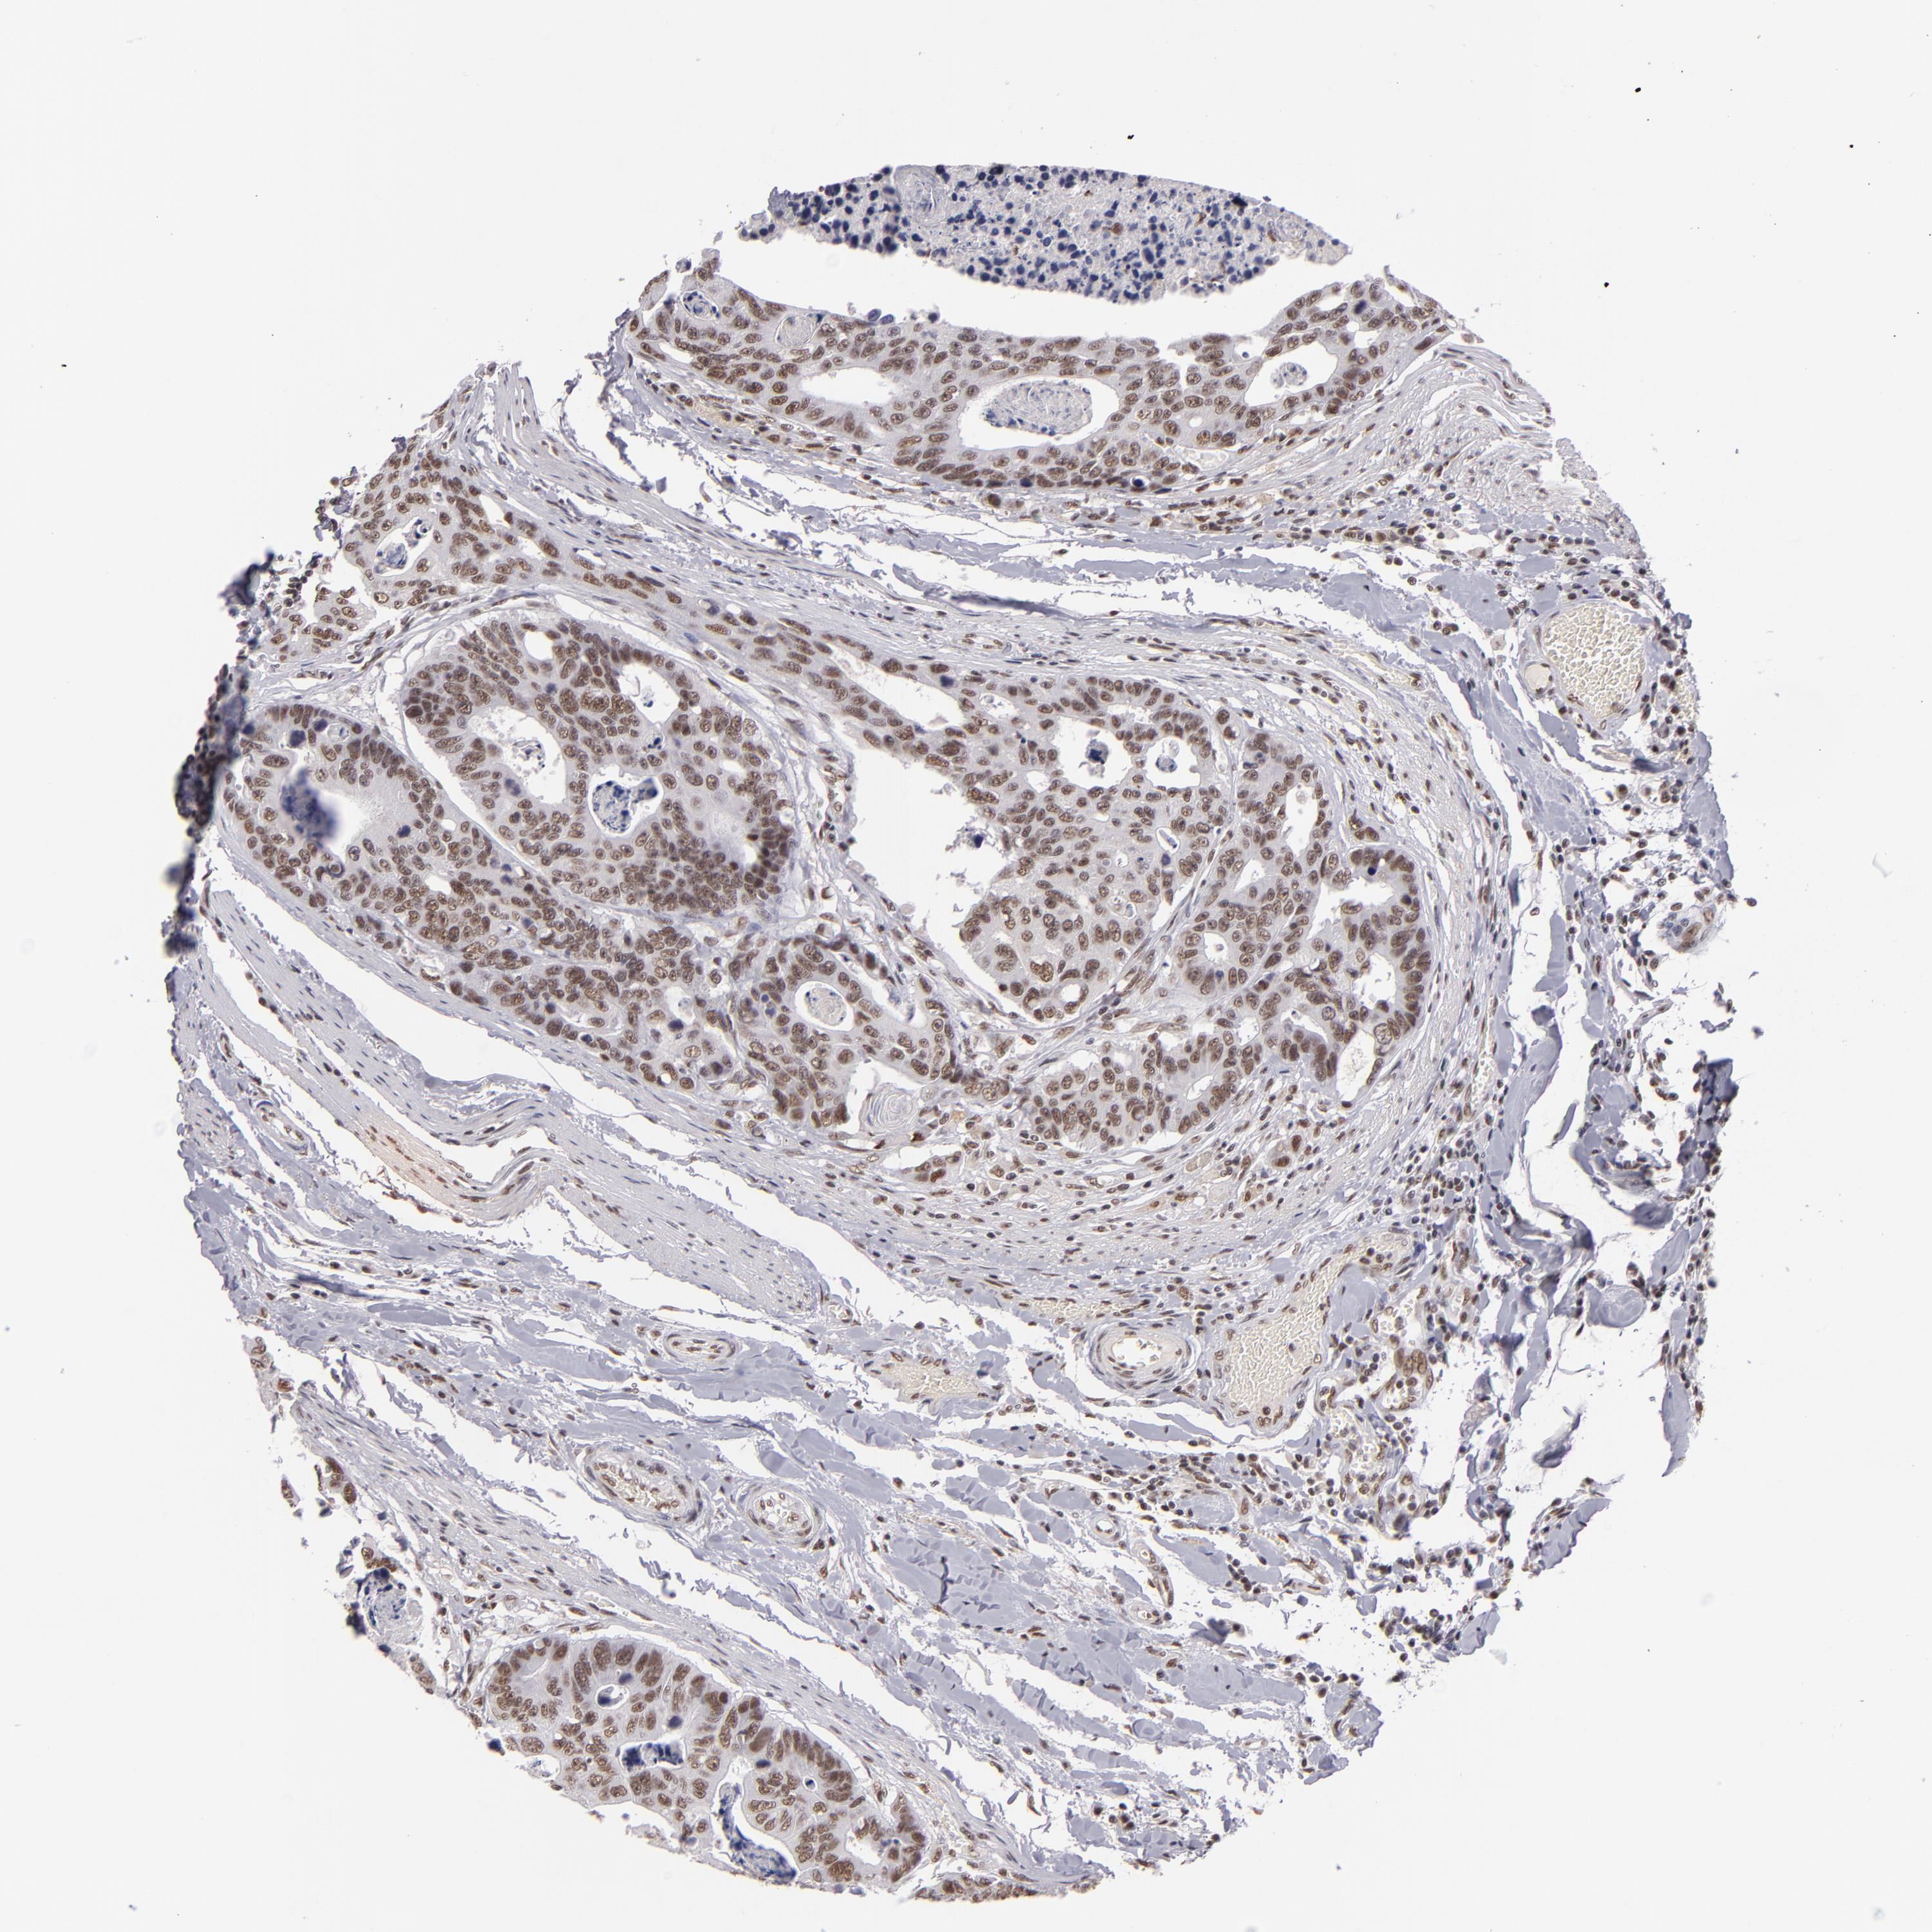

CANCER COLORECTAL CANCER Show tissue menu

ANTIBODIES

AND

VALIDATION